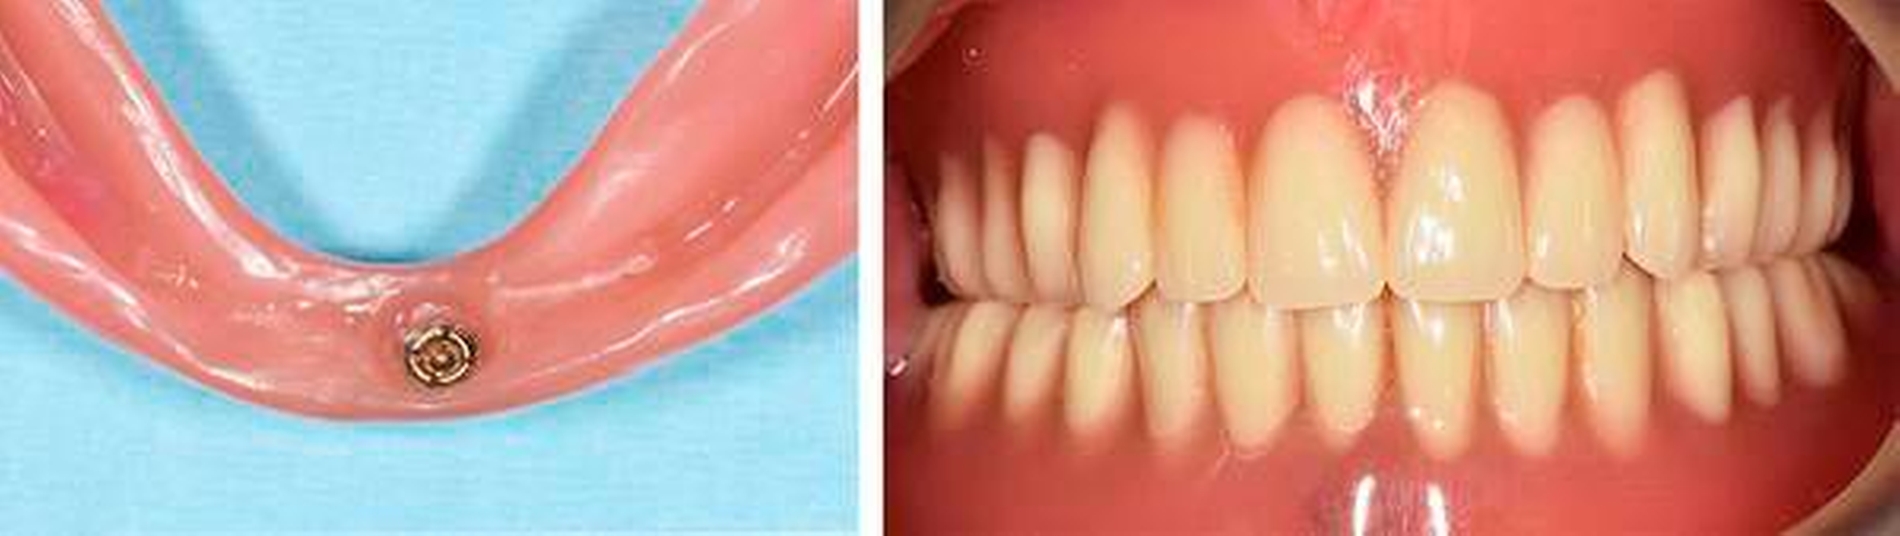

Anschließend sollte eine röntgenologische Kontrolle mittels Panoramaschichtaufnahme erfolgen. Nach einer Implantateinheilung von drei Monaten können chairside die Retentionselemente in den vorhandenen Zahnersatz eingearbeitet werden. Das Kugelkopfattachment (Gingivahöhe 1,5 mm, Camlog) wird mit einem manuellen Drehmomentschlüssel (Camlog) mit einem definierten Drehmoment von 30 Ncm eingesetzt (Abbildung 3).

Es folgt das achsengerechte Ausrichten der Matrize mit ovalem Retentionsdeckel (Dalbo-Plus ellipitic Cendres & METAUX SA) auf dem Kugelkopf (Abbildung 4).

Für das Einpolymerisieren der Matrize in den Kunststoff muss zunächst eine Aussparung regio 31/41 von lingual ausgeschliffen werden, so dass via Spiegel eine Platzbedarfskontrolle erfolgen kann. Die Oberfläche der Matrize sollte für einen stabilen Verbund zum Kunststoff im Rahmen einer Silanisierung und Silikatisierung vorbehandelt werden. Dafür kann die Prothesenbasis mit Aluminiumoxidpulver mit 2 bar mechanisch und mit einem Kunststoffprimer chemisch vorbehandelt werden. Danach kann das Einpolymerisieren in die Prothese mithilfe eines Kunststoffs für Provisorien (Luxatemp, DMG, Hamburg) erfolgen (Abbildung 5). Zu empfehlen ist, die Passung der modifizierten Prothese erneut mit einem Fließsilikon zu überprüfen. Die Patienten sollten wie üblich nach einer Eingliederung von neuem Zahnersatz Instruktionen zur Handhabung sowie zur Hygiene des Zahnersatzes erhalten und über einen regelmäßig notwendigen Recall aufgeklärt werden (Abbildung 6).